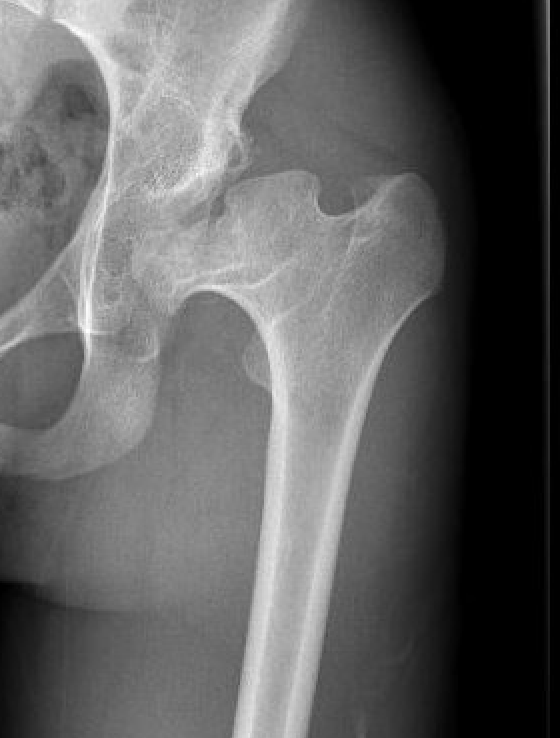

Technique

Option

- monoblock stem

- modular stem

Uncemented stem

Modular stem

Trochanteric slide